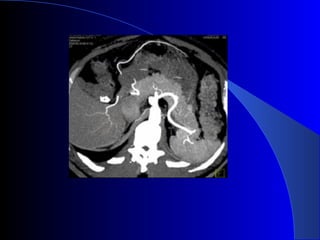

Estudios de imagen USG abdominal TAC helicoidal dinámica en tres fases: estándar de oro para diagnóstico y valorar resecabilidad CPRE RMN TEP Neoplasias páncreas. Rosesch Dietlen pag 545-560

Diagnóstico CLÍNICO: Avanzadoe incurable. LABORATORIO: Anemia, desnutrición, obstrucción biliar, hiperamilasemia. US: Sensibilidad: 80%, especificidad: 75%. (>3 cm). Ganglios, dilatación VB. TAC: Estudio inicial de elección. CPRE: Obstrucción del Wirsung. Dr. Nogueira de Rojas

Estudios de imagenUSG abdominal TAC helicoidal dinámica en tres fases: estándar de oro para diagnóstico y valorar resecabilidad CPRE RMN TEP Neoplasias páncreas. Rosesch Dietlen pag 545-560